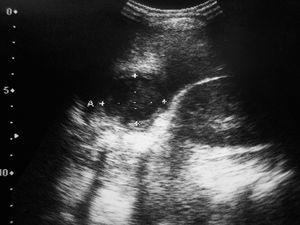

Ante este empeoramiento se realizan los siguientes exámenes complementarios: hemograma (hemoglobina, 11,7 g/dl; hematócrito, 33 %; plaquetas, 541.000/μl; leucocitos, 21.100/μl con 75 % neutrófilos, 14 % linfocitos, 9 % monocitos); PCR, 109 mg/l; bioquímica sanguínea y transaminasas normales y coagulación normal. Hemocultivo y urocultivo negativos. Radiografía de tórax, normal. Se realizó ecografía abdominal que mostró una lesión ocupante de espacio de 3,5 cm de diámetro en segmento VI hepático, de características sólidas, con bordes bien delimitados, compatible con absceso intrahepático (fig. 1).

Figura 1. Ecografía abdominal: masa sólida hipoecogénica, bien delimitada, situada en segmento VI hepático, de 3,5 cm de diámetro.